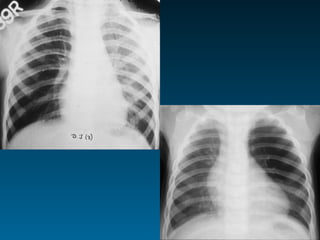

Οι συχνότερα χαμένες πνευμονίες